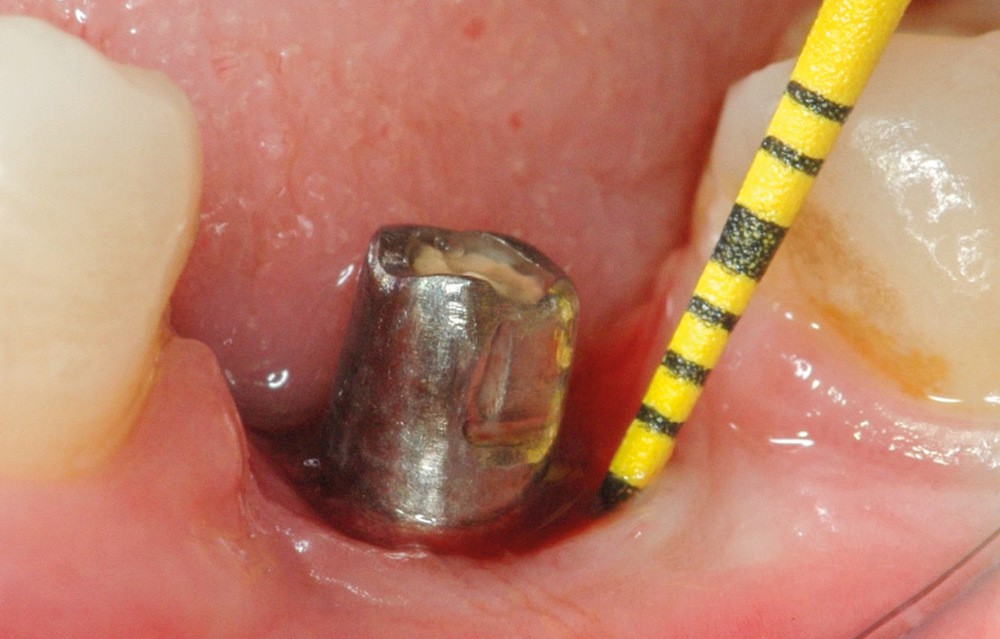

Chez ce patient, le traitement de la péri-implantite a comporté une chirurgie associant décontamination électrolytique de la surface implantaire, régénération osseuse guidée et enfouissement de l’implant. Le résultat à 2 ans est très moyen au vu du pourcentage de régénération osseuse obtenu. Comment peut-on prévoir un tel résultat alors que l’on a suivi les recommandations à la lettre, que l’on a utilisé les dernières technologies de décontamination, que l’on y a mis tous les moyens, que le patient est en bonne santé générale et qu’il vient en plus régulièrement aux séances de thérapeutique de soutien ? Le succès du traitement des péri-implantites n’est pas simple à obtenir, surtout quand un élément clé est compromis… la maintenance personnelle ! En effet le succès n’est possible que si le contrôle de plaque quotidien est optimal et, ici, ça n’était pas le cas. Le patient se brossait certes les dents, mais ne passait pas quotidiennement les brossettes, ce qui…